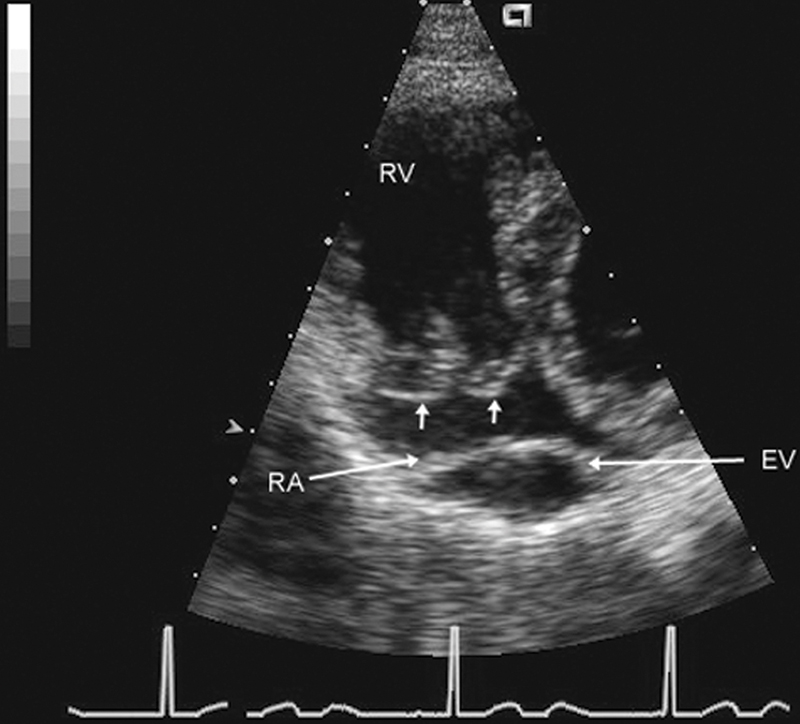

فحوصات تشخيصية لبعض امراض القلب والشرايين التاجية